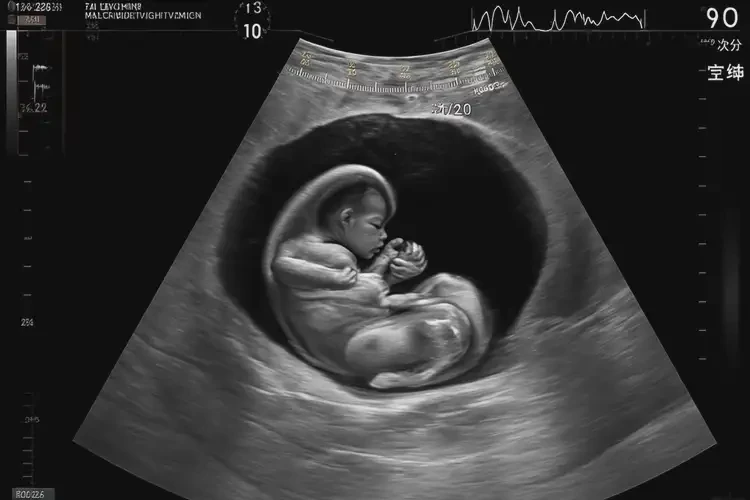

孕22周胎心90左右寶寶還能要嗎(圖1)

孕22周胎心90左右寶寶還能要嗎

胎心90次/分鐘在孕22周屬于異常情況,需要立即就醫(yī)評(píng)估胎兒狀況。

胎心率是評(píng)估胎兒健康的重要指標(biāo),正常范圍通常為110-160次/分鐘。在孕22周時(shí),胎心率持續(xù)在90次/分鐘左右可能表明胎兒存在缺氧或其他健康問題,需要及時(shí)進(jìn)行醫(yī)學(xué)干預(yù)和評(píng)估。